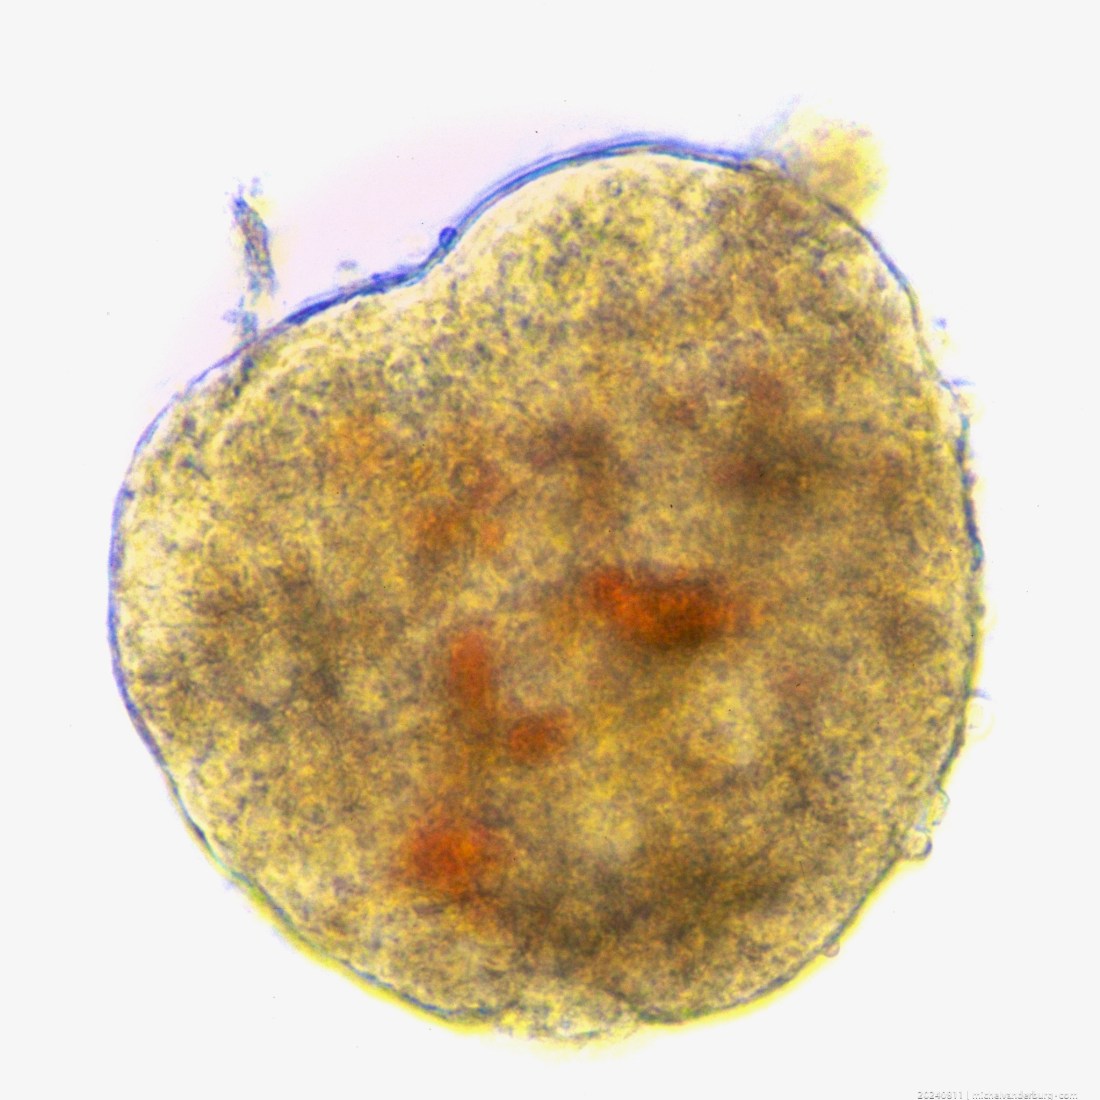

Shortly after starting our Islet Lab end 1986, I hand-picked and photographed this special big heart-shaped isolated islet of Langerhans with Uncle Scrooge McDuck’s ‘lucky #1 dime’ in mind.

It’s an Islet of Langerhans isolated from a rat pancreas. For pilot work, the first months while developing our islet project plan, islets were isolated from rat pancreases.

I had started developing our basic lab methods… like eg. measuring the insulin secretion capacity and insulin content of isolated islets. A custom-made glass pipet was used to hand-pick and transfer the islets to little polypropyleen ‘Eppendorf’ tubes for insulin secretion tests with glucose stimulation.